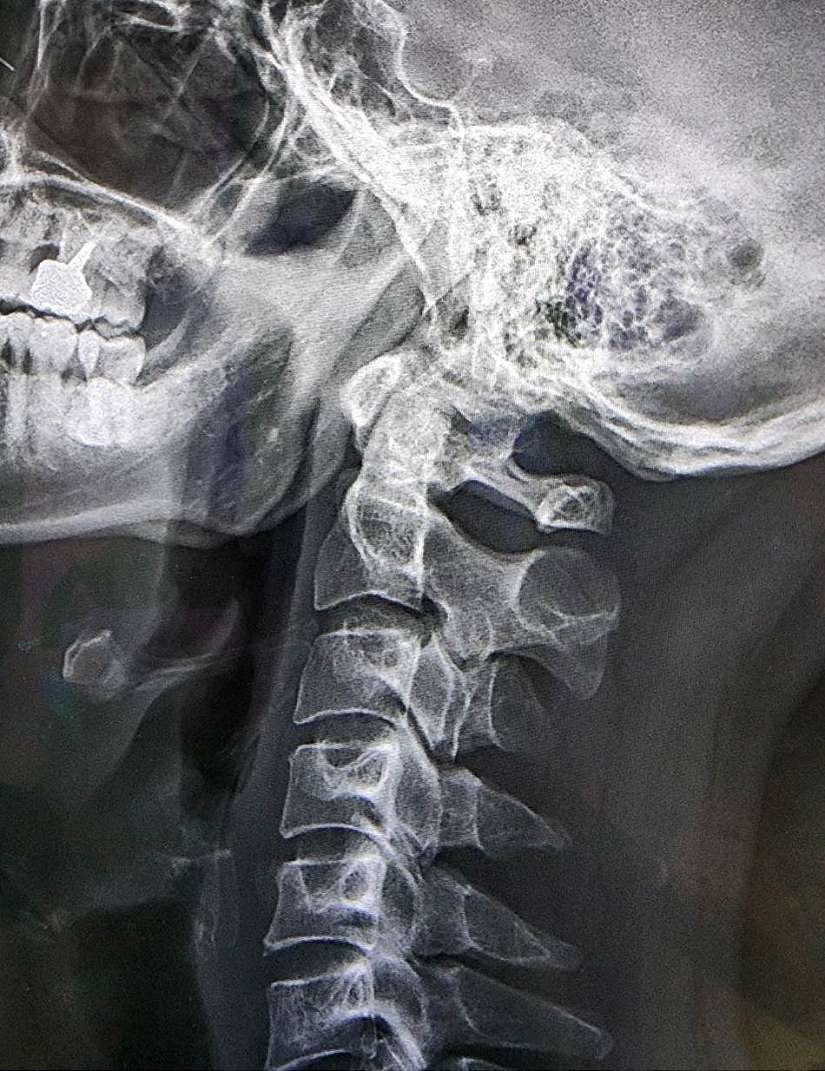

最近因手肘痠痛前往臺北市立聯合醫院中興院區復健科就診,看診當天剛好頭痛發作,自行吃了止痛藥也無法改善,經門診問診後執行X光檢查,側面X光影像顯示頸椎變直(正常應為C形)但無其他異常,整體判斷應為“頸因性頭痛”,與患者討論後執行局部類固醇注射,頭痛瞬間緩解。